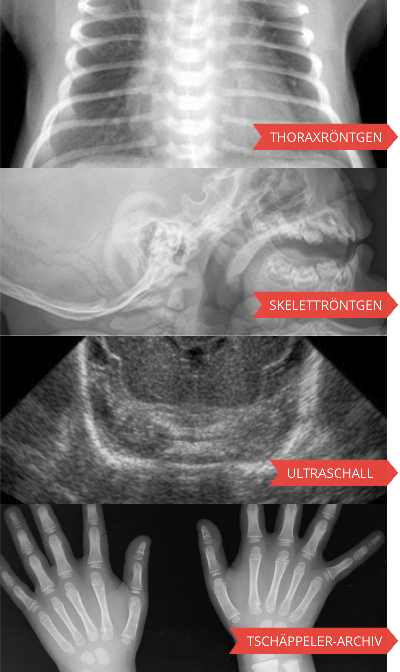

Radiosurf

Pedirad